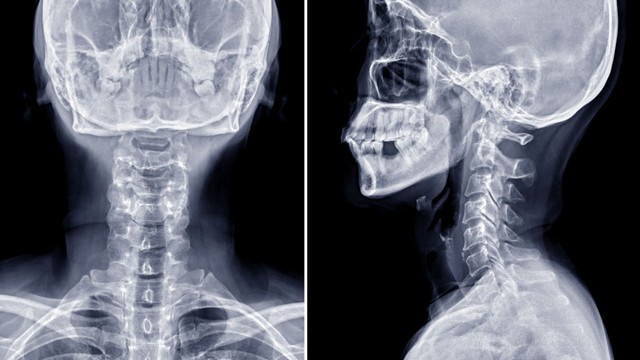

X quang